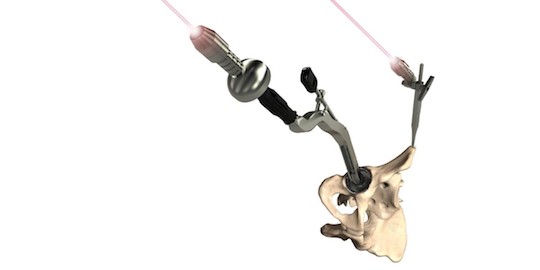

It is vital during total hip replacement surgery that the implant hardware is aligned correctly to limit the possibility of later complications. Every patient has a unique pelvic motion and Optimized Ortho developed dynamic modelling technology which provides pre-surgical information on the patient’s predicted biomechanics.

Optimized Ortho engaged Park Industrial to enable the second stage of their implant positioning system. We created surgical guides uniquely shaped to match the pelvis of each patient that were derived from X-ray and CT scan data. These guides are then fabricated from the latest 3D printing techniques using biocompatible materials.

Park Industrial developed an automated system of guide design that was created using Python scripts and the Solidworks API. This helped to realise the commercial viability of the technology.